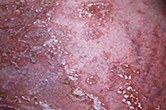

看图读懂不同类型的皮炎

专家提醒:皮炎最明显的症状就是瘙痒,但是引起皮炎的病因各有不同,不能一概而论,需要专业的皮肤专家综合诊断。